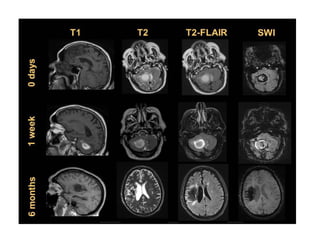

e) Chronic Infarct :

-In the chronic stage of infarction , cellular debris and

dead brain tissue are removed by macrophages and

replaced by cystic encephalomalacia and gliosis

-Infarct involvement of the corticospinal tract may

cause mass effect , mild hyperintensity on T2 and

eventual atrophy of the ipsilateral cerebral peduncle

& ventral pons due to Wallerian degeneration , these

changes can first be seen in the subacute phase with

atrophy being predominant feature in the chronic

stage (See later)

-DWI has usually returned to normal in the

chronic stages

-Occasionally , cortical laminar necrosis can

develop instead of encephalomalacia , cortical

laminar necrosis is a histologic finding

characterized by deposition of lipid-laden

macrophages after ischemia that manifests on

imaging as hyperintensity on both T1 & T2

T1+C shows a corresponding area of parenchymal enhancement